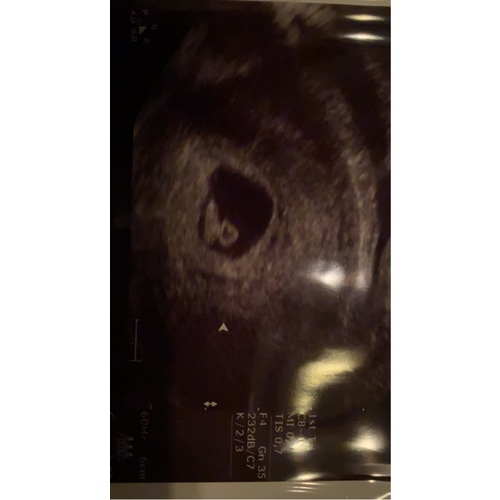

Bij mij is de echo inwendig genomen. Dan zou het volgens deze methode een meisje worden denk ik? Benieuwd wat de nipt als resultaat gaat geven ☺️